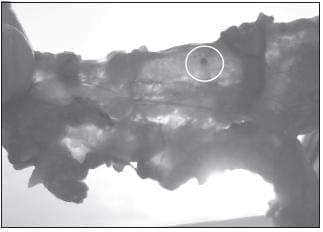

FIGURA 2. El tejido aclarado permite la identificación a trasluz de las estructuras ganglionares.

FIGURA 3. El azul de metileno permite, además, identificar los ganglios de manera visual que, de otra manera, no sería fácil ni por la palpación ni por la visualización directa del ganglio.